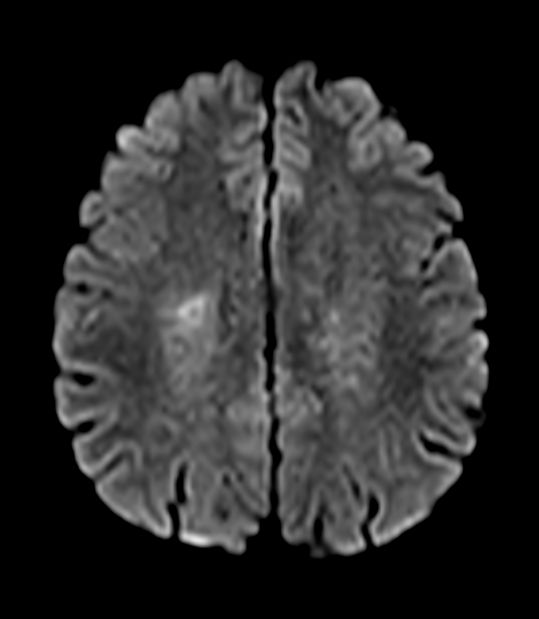

Brain - White matter lesions

Fast and high quality brain imaging for a patient with white matter lesions. AI based SmartSpeed is utlized to shorten scan time without compromise in image quality. Advanced 3D TSE imaging technique are used to acquire high resolution data in multiple directions in only one single scan.

Axial DWI b1000